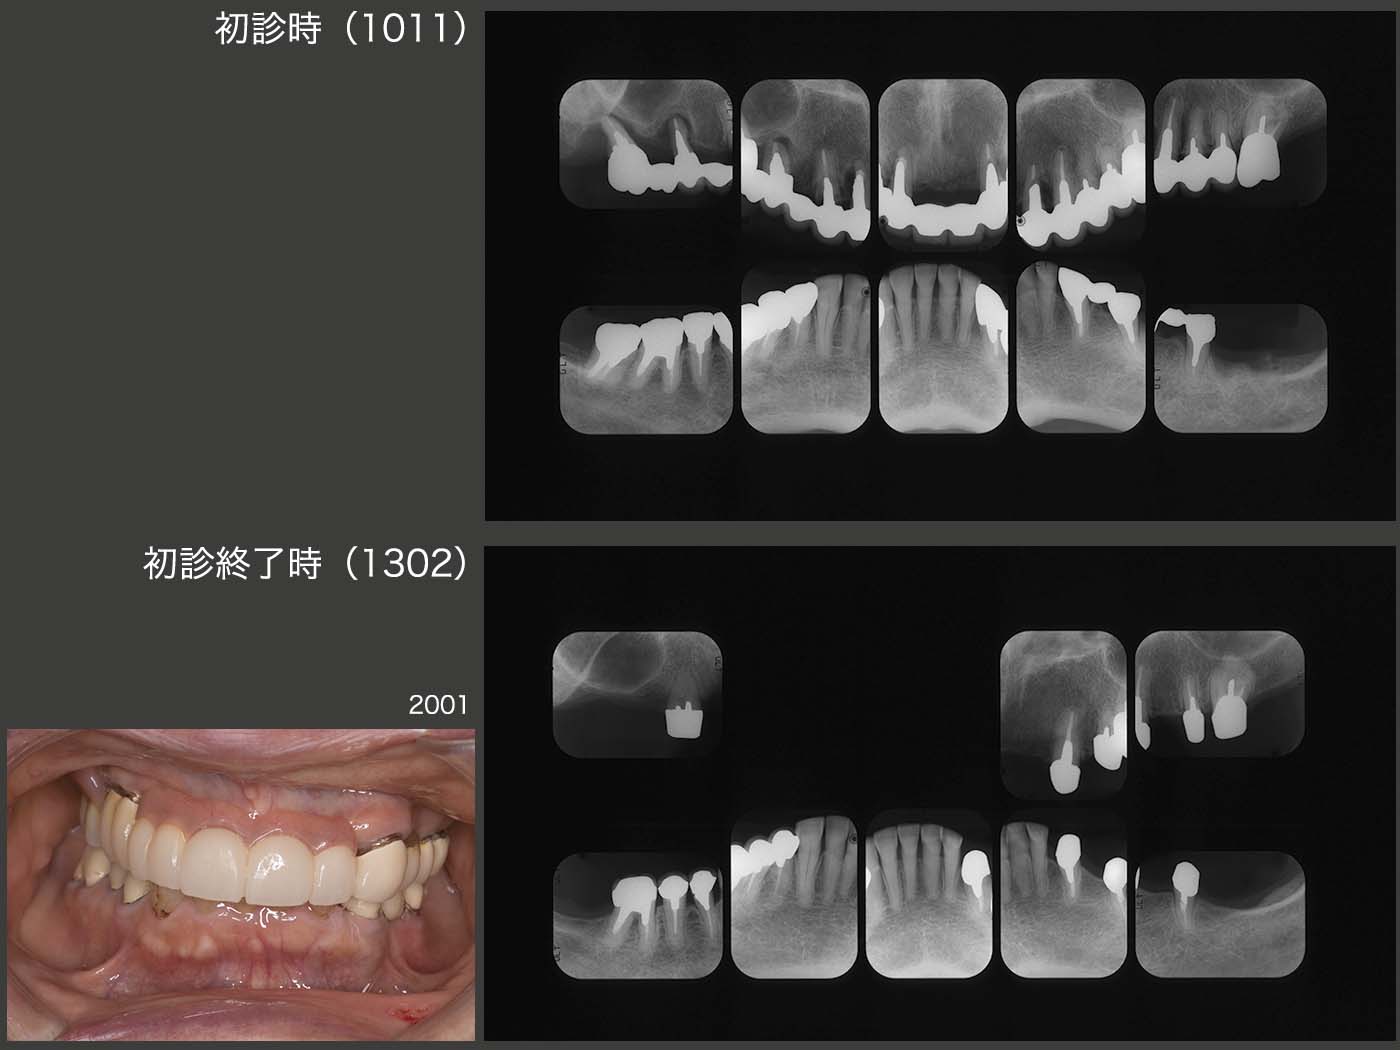

4.移植でやり繰りし、義歯を回避

2009年2月初診,26歳の女性.主訴は義歯を入れて欲しい.とにかく歯医者嫌いで恐怖心が強い.そうでなければここまで放置しないはずである.幼児期に治療を受けた嫌な思い出がトラウマになって歯医者にかかれない人は結構いると思われる.勇気を振り絞って来院したことをまずは褒め,とにかく信頼関係の構築に主眼を置き,徐々に治療を行っていった.右下の残根を抜歯し,そこに義歯を装着することは簡単だが,右下犬歯にクラスプが見えるのは審美的に耐えられないであろう.それでは,インプラントを用いるかといっても,費用が高く経済的に厳しい.

そこでまず,10年3月に左上7の残根を抜歯し,口蓋根のみを再植した.つぎに右上7を分割抜歯したところ,3根ともに歯根膜が付着しており,条件が良かった.そこで,それぞれを右下に移植した.なお右下7は,根長が短くさすがに保存できず,この症例で唯一抜歯となった歯である.抜歯後の顎堤が細かったが,3根を一直線に並べることで対応できた.

残りの治療を行い,初診から3年4ヵ月を費やし,何とか治療を終了することができた.

初診時と初診終了後約1年のパノラマX線写真の比較(妊娠したため,初診終了時のパノラマX線写真は撮らず).私自身も治療結果には満足している.しかし,問題はその後である.患者さんは最初の1回,リコールに応じたが,その後は一度もリコールに応じてくれない.結婚し,子供が2人出来,仕事も常勤でこなし,とても忙しいとのことである.たまに近所で会うと,私が“一度見せてください” 彼女が“分かりました”とは言うもののもう5年,一度も来院されていない.口の中がどうなっているかとても心配であるが,本人が来てくれない限りどうしようもない.“歯”・“口”・“人”というが,つくづく“人”との関係が一番難しいと痛感する次第である.